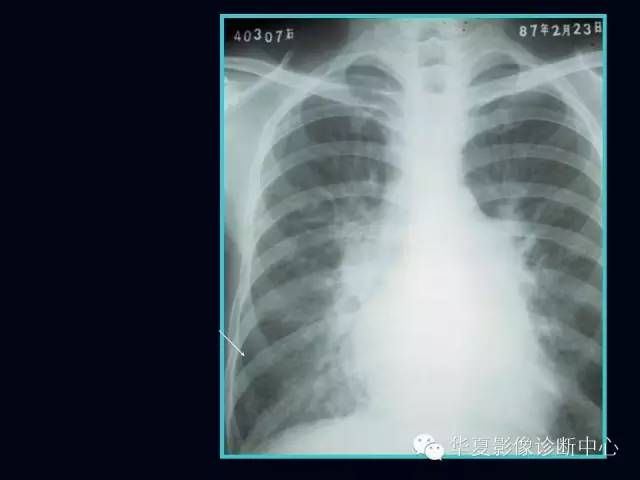

肺部血管性疾病

【PPT】肺部血管性疾病